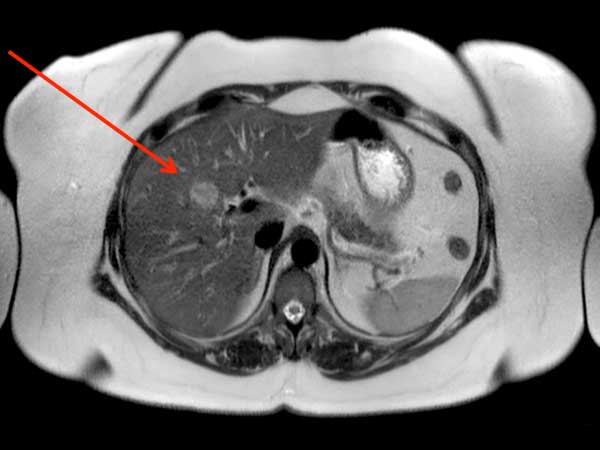

Liver imaging - Obese patient